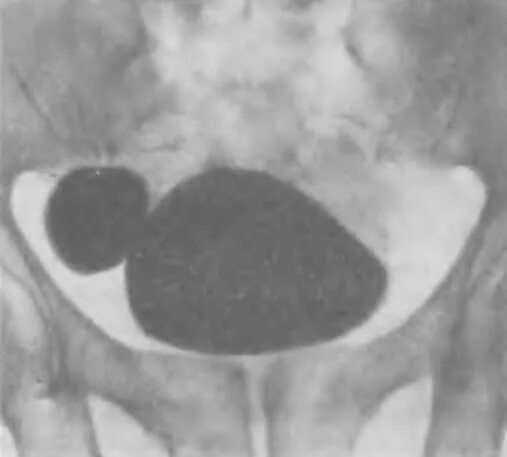

Дивертикул мочевого пузыря что это такое